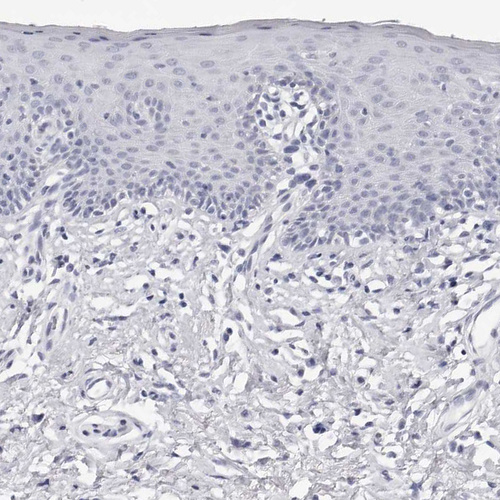

Immunohistochemistry analysis in human testis and liver tissues using HPA028615 antibody. Corresponding INSL3 RNA-seq data are presented for the same tissues.